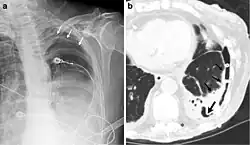

El diagnóstico del fibrotórax suele basarse en una historia clínica adecuada combinada con técnicas de imagen como la radiografía de tórax o la tomografía computarizada.[3] Estas herramientas detectan el engrosamiento pleural y la fibrosis alrededor de los pulmones.[7] La presencia de una corteza engrosada, con o sin calcificación, es una característica común en las imágenes.[3] Las tomografías computarizadas diferencian mejor si el engrosamiento se debe a depósitos de grasa o a fibrosis verdadera.[3]

En casos graves, el pulmón afectado puede perder volumen[7] y el mediastino puede desplazarse hacia el lado afectado.[3] Una reducción del tamaño de un lado del tórax en las imágenes sugiere cicatrización crónica.[6] Los signos de la enfermedad subyacente que causa el fibrotórax también se observan ocasionalmente en la radiografía.[6] Las pruebas de función pulmonar suelen mostrar hallazgos compatibles con una enfermedad pulmonar restrictiva.[6]

Radiografía de tórax (izquierda) y tomografía computarizada (derecha) que muestran fibrotórax. -